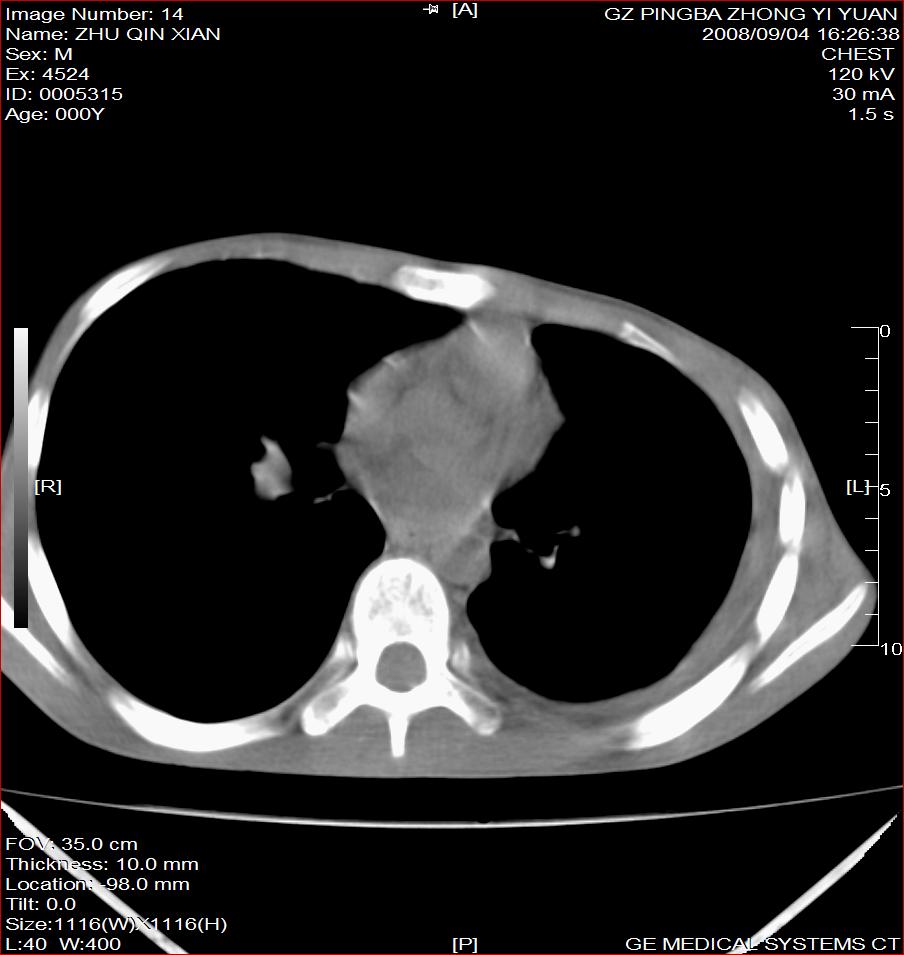

以下是引用随光逐影在2008-9-4 20:05:00的发言:[br]1)考虑两肺结核。2)左侧胸膜炎(胸膜肥厚、粘连,胸腔积液)。3)左侧局限性气胸。

以下是引用子十在2008-9-4 19:34:00的发言:[br]左上肺结核并空洞及双肺播散。节段性肺不张、胸腔积液、胸膜肥厚粘连。[br]